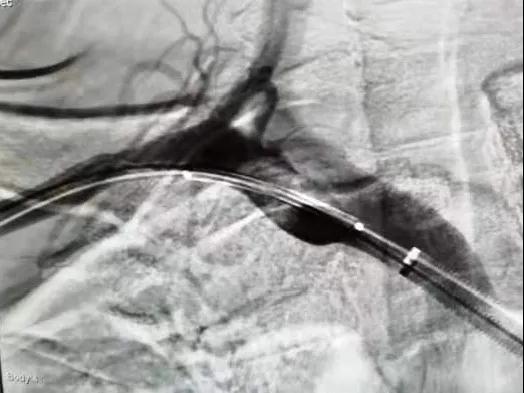

1616144481584106.jpg

造影見大斑快堵塞開口